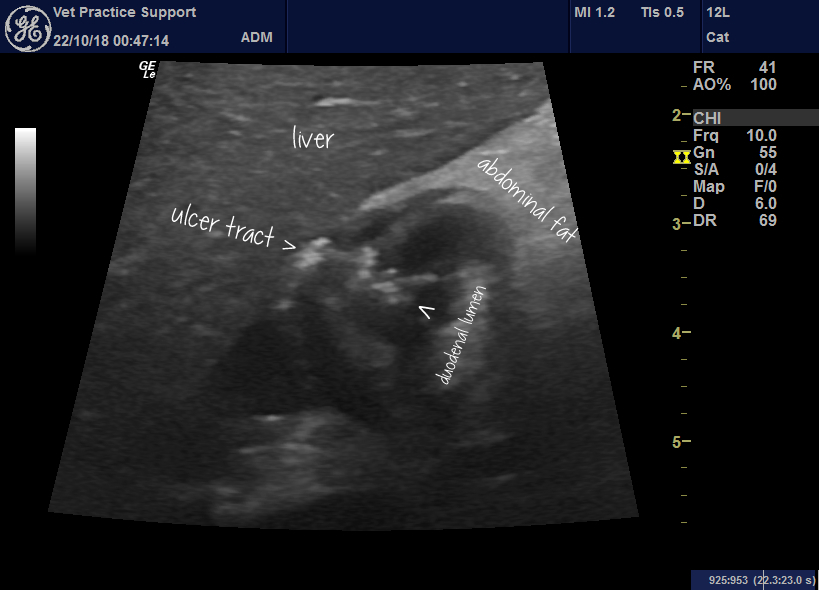

My observation is that, amongst UK veterinary practices and institutions, there is considerable variation in protocols on when to give prophylactic PPIs to dogs (and to a lesser extent) cats who are prescribed glucocorticoids. The mechanisms through which glucocorticoids might promote ulcer formation have been proposed to include inhibition of gastric mucus synthesis, enhancement of … Continue reading